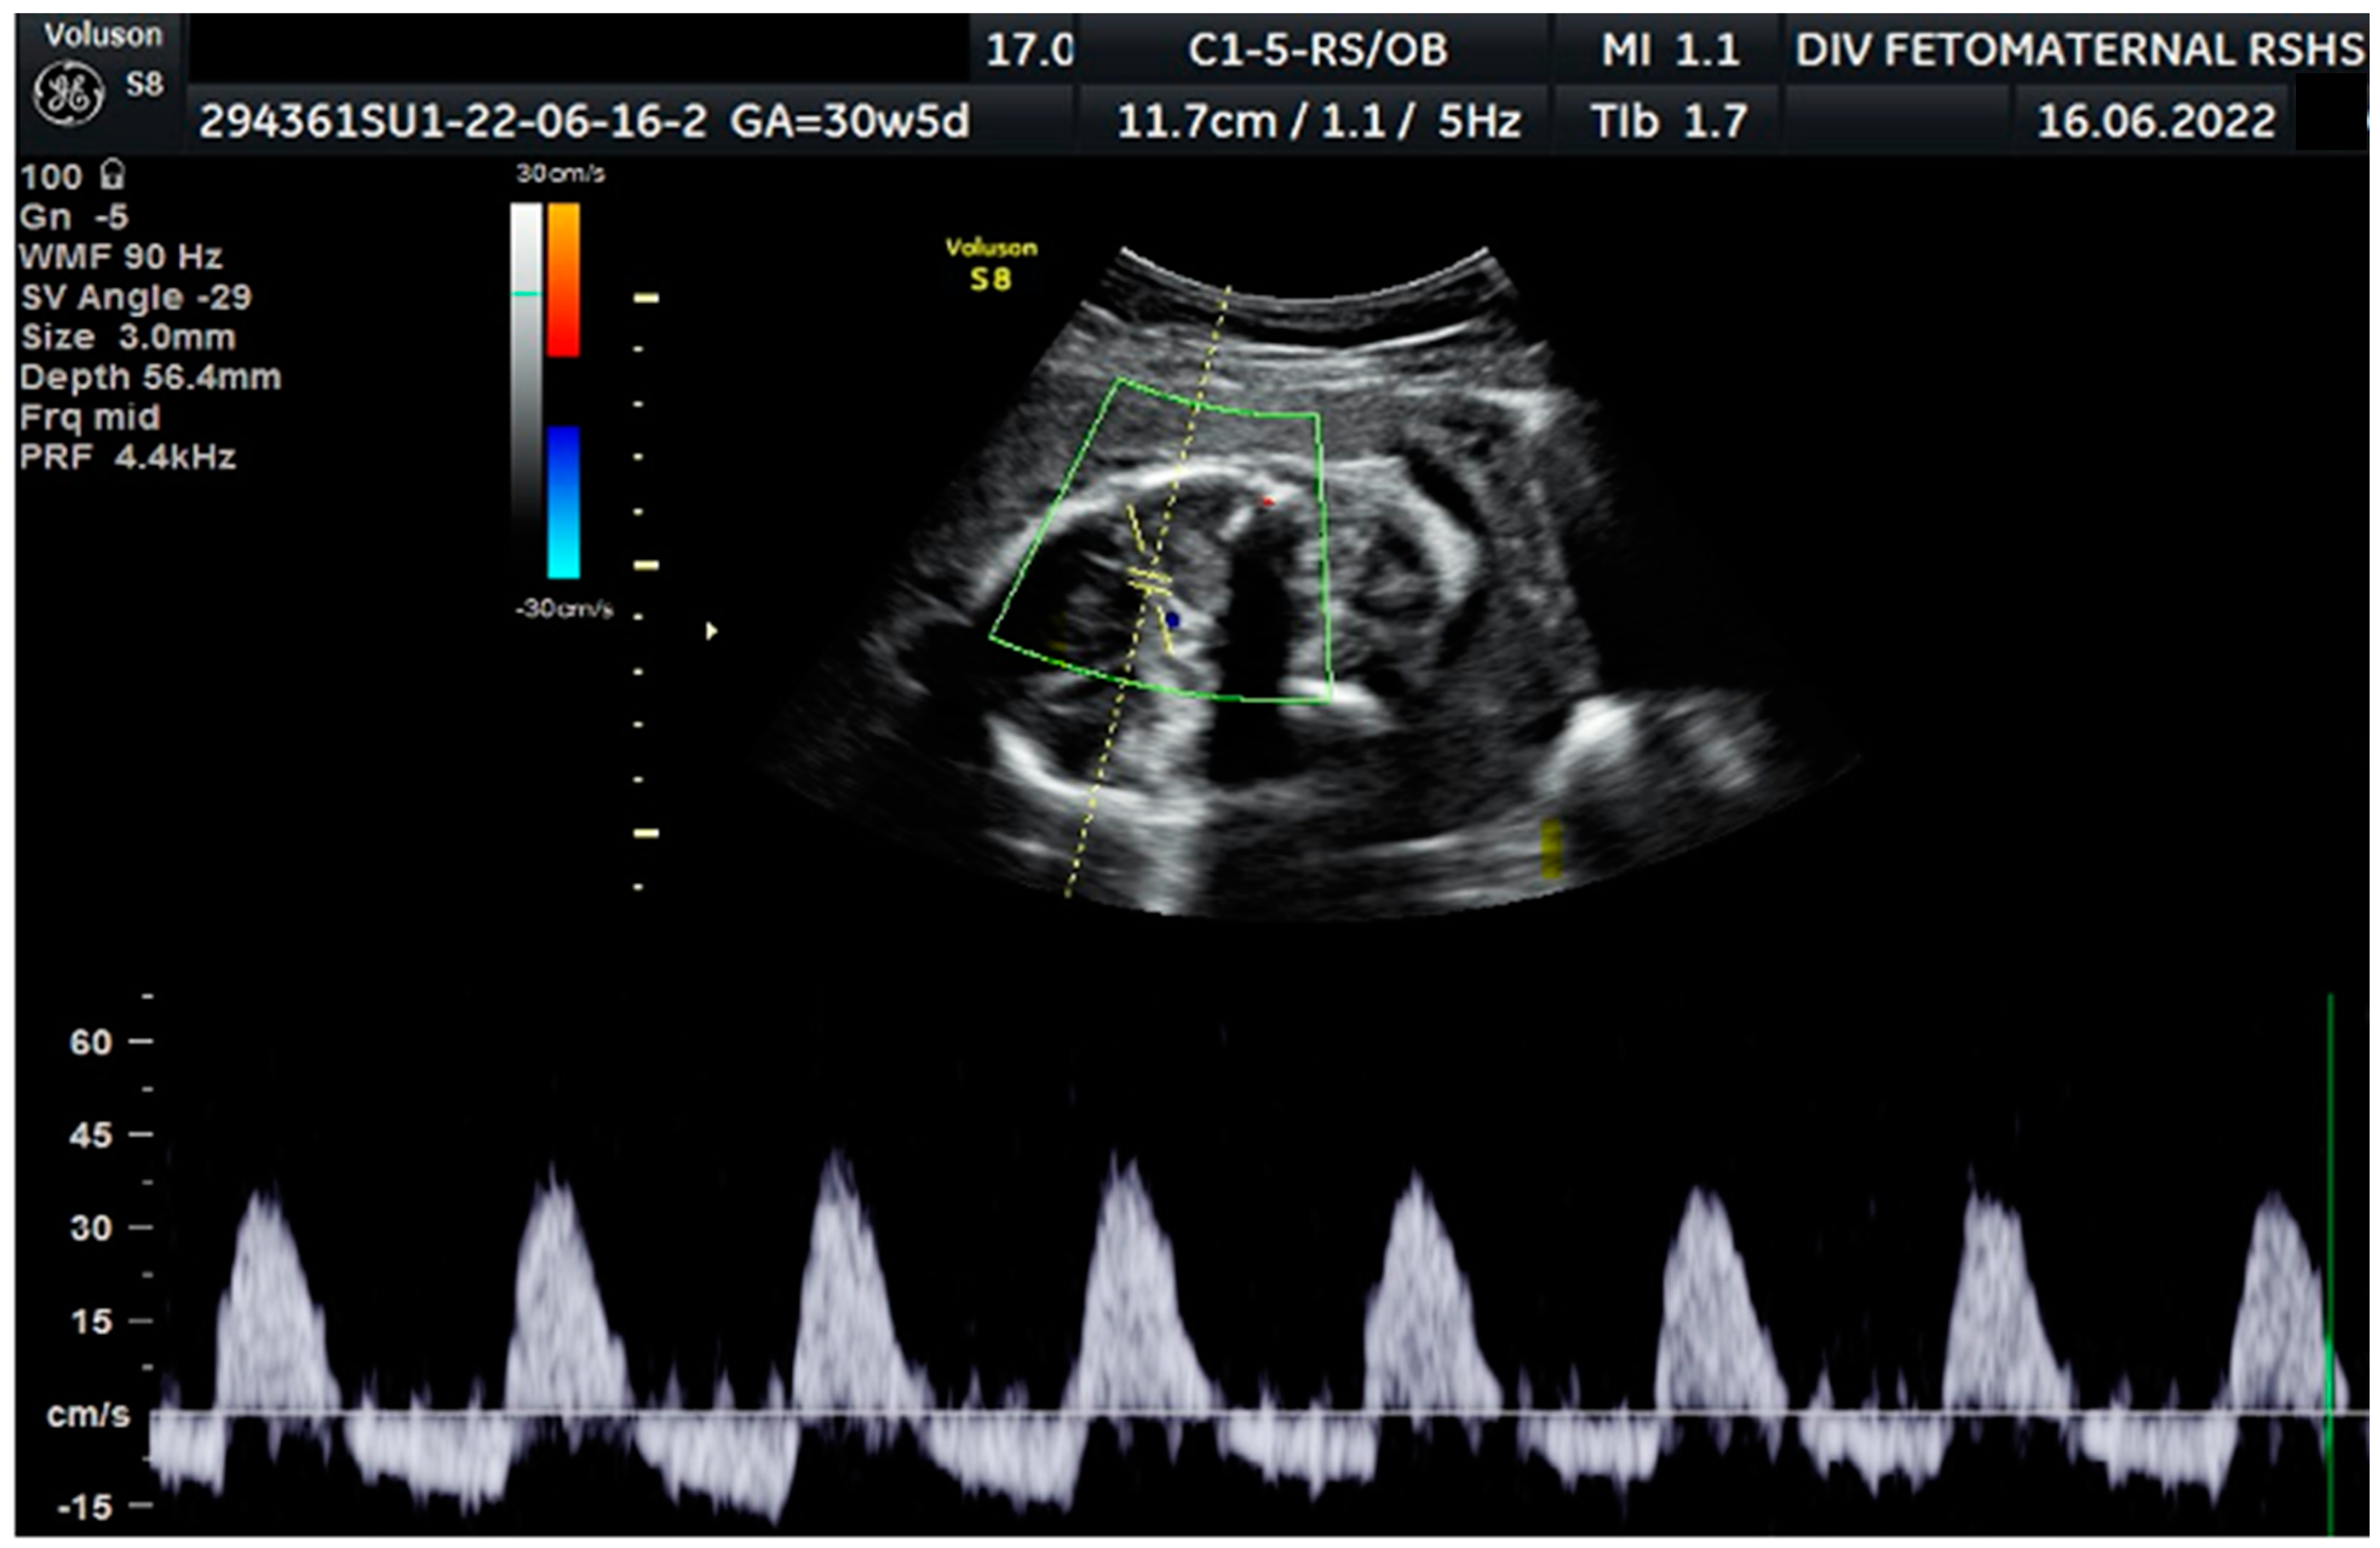

Color Doppler examination of the MCA revealed a peak systolic velocity of 42.33 cm/s, which is 1.045 times the median (the normal range is 40.5 cm/s for this gestational age), with persistent reversed end diastolic flow (Figure 2). The umbilical artery pulsatility index (PI) was 0.99, and RI was 0.63, with an S/D ratio of 2.71. There was notching on the right uterine artery, with a PI of 2.11. Notching was also found on the left uterine artery, with a PI of 1.58 (Figure 3). Laboratory results were within a normal range.

Figure 2. Reversed end diastolic flow in the middle cerebral artery.